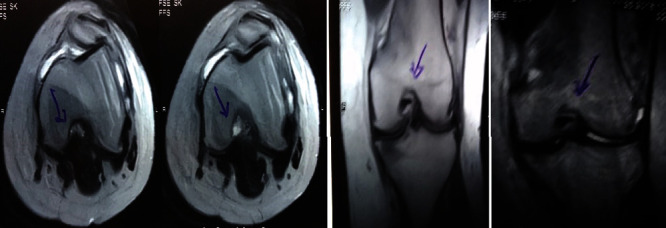

治療后一個月進行隨訪。在第一次細(xì)胞治療后,患者的疼痛明顯減輕。第二次療程后,她沒有疼痛,并注意到運動范圍有所改善。持續(xù)的物理治療也觀察到下肢肌肉力量的增加。從治療開始(11個月前)到最后一次隨訪(4個月前),患者按照建議的飲食和基于運動的方案減重了11公斤。因此,她現(xiàn)在整體身體健康,能夠更舒適地進行日常生活活動。表3顯示治療前后的MRI檢查結(jié)果。人物的圖1和的和圖2顯示半月板撕裂的治療前和治療后(1年后)圖片。觀察到損傷程度的改善圖2。